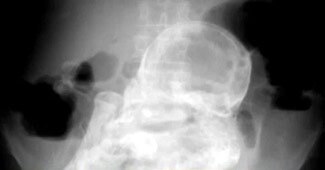

36 साल बाद महिला के गर्भाशय से निकाला गया अजन्मे शिशु का कंकाल

अपने किस्म के एक अनोखे ऑपरेशन में डाक्टरों के एक दल ने 36 साल बाद एक 60 वर्षीय महिला के गर्भाशय से उसके अजन्मे शिशु का कंकाल आपरेशन के जरिए निकाला. किसी महिला के शरीर में एक्टोपिक भ्रूण के रहने की यह संभवत: सबसे लंबी अवधि है.

महिला का ऑपरेशन करने के बाद डाक्टरों की टीम ने पाया कि बड़ी गांठ में एक पूर्ण विकसित शिशु का कंकाल था. यह गांठ गर्भाशय, आंत और पेशाब की थैली के बीच थी और आसपास के सभी अंगों के साथ गहरे से सटी हुई थी. डॉ. अख्तर ने बताया, 'भ्रूण की रक्षा करने वाला गर्भाशय का पानी हो सकता है सूख गया हो और नरम उत्तक समय बीतने पर तरल हो गए और थोड़े से पानी के साथ केवल हड्डियों का एक थला सा बचा था.